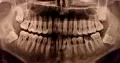

Разошлось мнение двух врачей: одна считает, что кариес на шестнадцатом есть, вторая, что его нет. На рентгене, на шестнадцатом виден темный участок, то есть, скорее кариес есть, чем его нет.

С вашей точки зрения он скорее есть, чем его нет? (речь идет не о поверхностном кариесе, который на рентгене нельзя увидеть, а о более глубоком: среднем или глубоком). Снимок был сделан до лечения.

На снимке в области семнадцатого и двадцать шестого зуба, под пломбой, наблюдается полость, которая неграмотно препарирована перед установкой пломбы, чувствительность и некий дискомфорт при надкусывании или пережевывании твердой пищи связано именно с этим. Что касается шестнадцатого зуба, я считаю, что полость имеется, но все-таки необходим еще и очный прием.